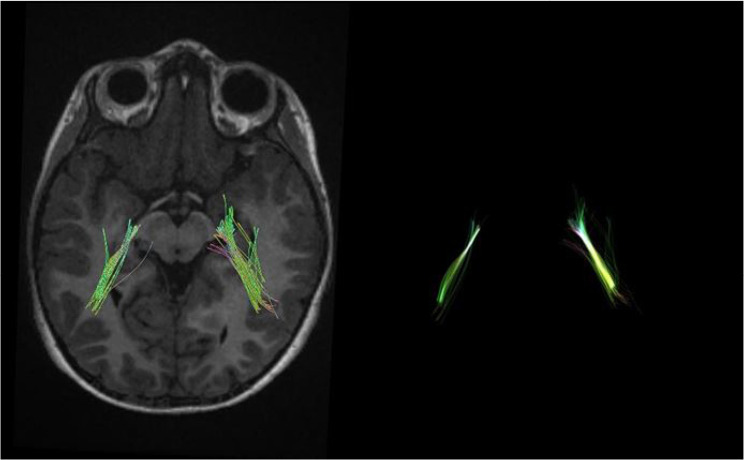

Methods: Twenty-two children including 11 subjects with SNHL aged 1-4 years and 11 healthy children were examined as controls. Then, DTI-derived parameters, such as fractional anisotropy (FA), mean diffusivity (MD), axial diffusivity (AxD), and radial diffusivity (RD), and volume of fiber tracts were extracted from the inferior longitudinal fasciculus, acoustic radiation, and uncinate fasciculus.

Results: The results showed an increase in MD, RD, and AxD as well as a decrease in FA, volume, and diameter of auditory-pathway-related fiber tracts. Interestingly, there was an increase in the FA of acoustic radiation.